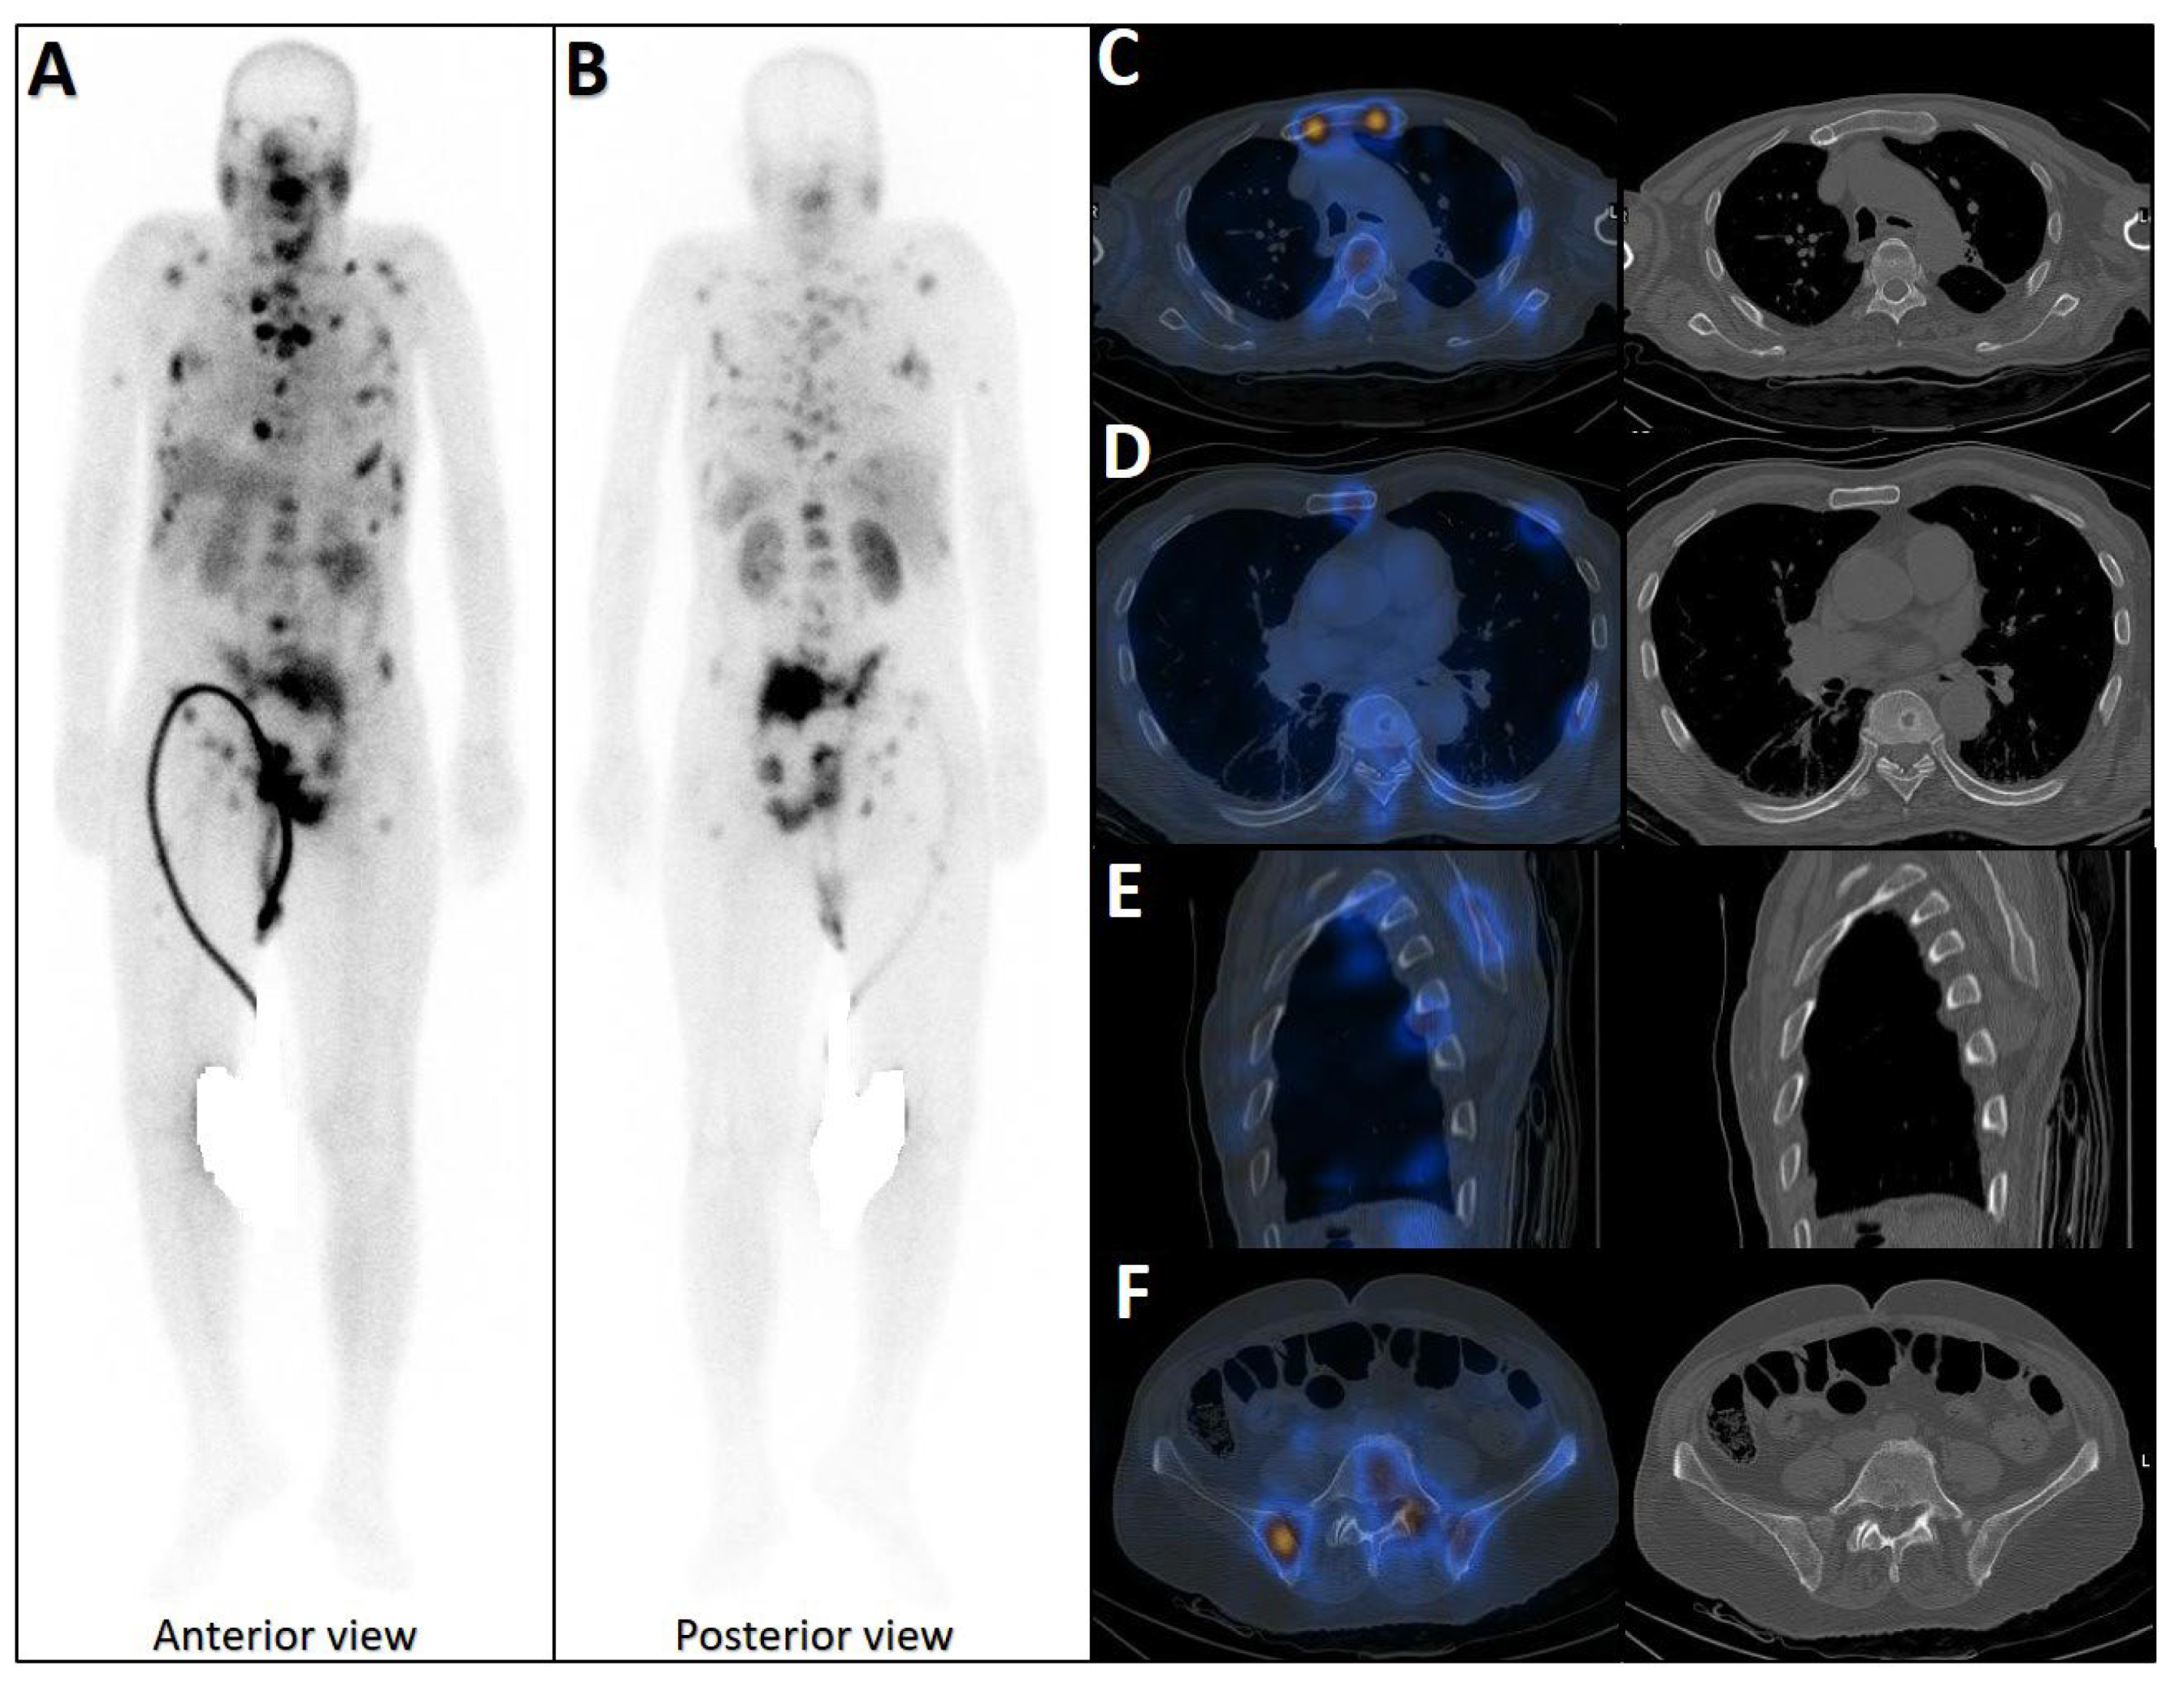

- Serani, F.; Fendler, W.P.; Castellucci, P.; Berliner, C.; Barbato, F.; Herrmann, K.; Farolfi, A.; Fanti, S. A Retrospective Multicenter Analysis of the Incidence of Bone-Only Disease at PSMA PET/CT in Castration Resistant Prostate Cancer Patients. Cancers 2023, 15, 2208. [Google Scholar] [CrossRef]

- Bauckneht, M.; D’Amico, F.; Albano, D.; Balma, M.; Cabrini, C.; Dondi, F.; Di Raimondo, T.; Liberini, V.; Sofia, L.; Peano, S.; et al. Composite Prediction Score to Interpret Bone Focal Uptake in Hormone-Sensitive Prostate Cancer Patients Imaged with [18F]PSMA-1007 PET/CT. J. Nucl. Med. 2024, 65, 1577–1583. [Google Scholar] [CrossRef]

- Seifert, R.; Telli, T.; Opitz, M.; Barbato, F.; Berliner, C.; Nader, M.; Umutlu, L.; Stuschke, M.; Hadaschik, B.; Herrmann, K.; et al. Unspecific 18F-PSMA-1007 Bone Uptake Evaluated Through PSMA-11 PET, Bone Scanning, and MRI Triple Validation in Patients with Biochemical Recurrence of Prostate Cancer. J. Nucl. Med. 2023, 64, 738–743. [Google Scholar] [CrossRef]